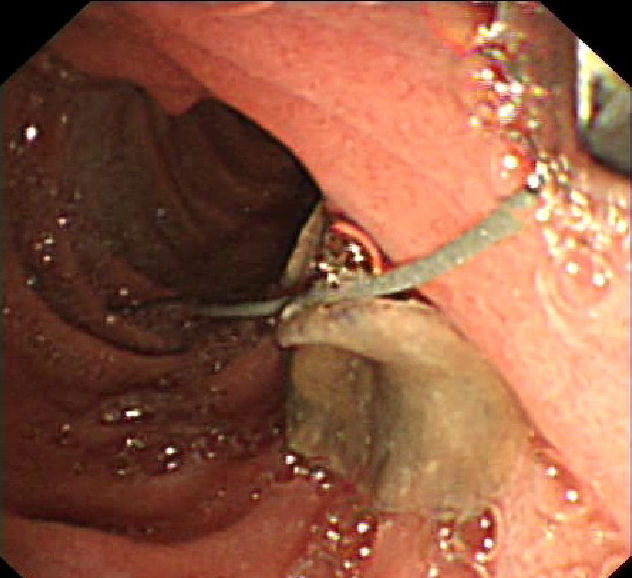

A 27-year-old Egyptian male with no significant comorbidities presented with history of episodic, recurrent abdominal pain of 4 years duration to our clinic at King Abdul Aziz specialist hospital Taif, a tertiary care centre in the western region of Saudi Arabia. Patient described pain as colicky, remaining for 1–2 hours necessitating intravenous analgesics predominantly in the upper abdomen. His abdominal pain had no reference or radiation and there was no jaundice associated with it. Patient had been admitted four times in various hospitals during this period and every time basic laboratory evaluation including liver function tests and serum amylase were within normal limits. His ultrasound examination had been within normal limits on each occasion he was hospitalized for his abdominal pain. Patient denied any high risk behavior or drug abuse. Over this period he had stable appetite and constant weight. On examination he was conscious oriented and he had stable vitals. There was no icterus, or lymphadenopathy. His systemic examination was unremarkable. Laboratory data revealed normal hemogram, normal liver function tests and his abdominal ultrasound was also within normal limits. There were no eggs or ova in his stool examination. Keeping in view recurrent biliary colics magnetic resonance cholangiopancreatography (MRCP) was done which showed a doubtful filling defect in the common bile duct but intra-hepatic biliary radicals were not dilated. There were no gall stones and the rest of the viscera were within normal limits. Endoscopic retrograde cholangiopancreatography (ERCP) was undertaken which revealed normal papilla. Selective common bile duct (CBD) canulation was done and cholangiogram revealed a filling defect in the lower end of common bile duct. There was mild dilatation of the common bile duct (Figure 1 [Fig. 1]) however, biliary radicals were not dilated. Sphincterotmy was done and CBD was sweeped with biliary balloon and a live Fasciola hepatica was seen coming out of the common bile duct (Figure 2 [Fig. 2], Figure 3 [Fig. 3]). Later using biopsy forceps the worm was taken out of duodenum and confirmation of the species, Fasciola hepatica, was made by the microbiology department of the hospital. Patient was given two tablets of triclabendazole 250 mg (manufactured by Novartis) after the procedure. Following therapeutic ERCP patient became symptom free and is attending our clinic for last 11 months now.

Figure 2: Fasciola coming out of CBD

Figure 3: Complete extraction of Fasciola in duodenum by ERCP